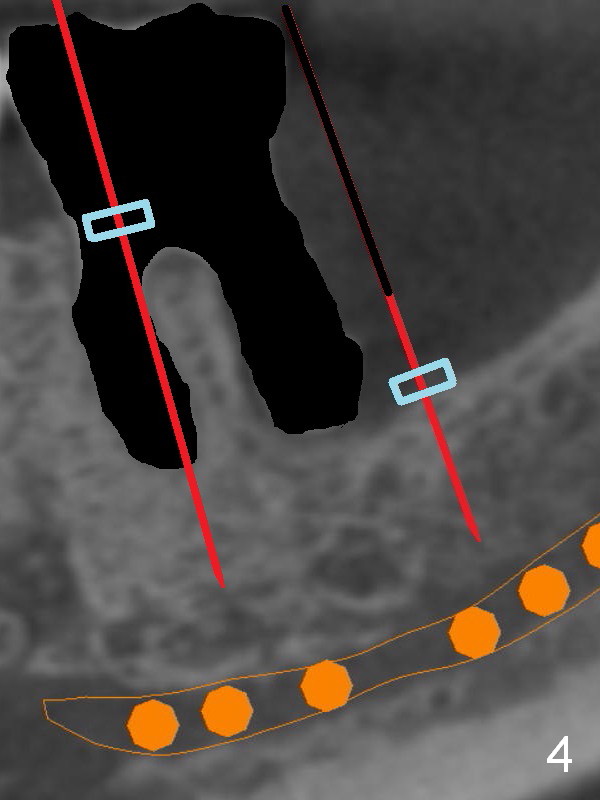

There is severe bone resorption around the distal root of the lower left 1st molar of the 56-year-old man (WG), while the loss of the 2nd molar is associated with limited bone height (Fig.1). A 5x14 mm implant will be placed at the mesial socket of #19 and 5.9 or 6.4x6 mm one is at the mesial site of #18 (Fig.7-9). Use a 2 mm pilot drill with 6 mm stopper from Sinus Master Kit (with extension) to initiate osteotomy at #18 immediately distal to the crown of #19, parallel to the long axis of the latter (Fig.2). After inserting a parallel pin at #18, extract the tooth #19 (Fig.3, antibiotic pending) and start osteotomy with a 2 mm pilot drill with 14 mm stopper (Fig.4). Insert the calibrated parallel pin at #19 (Fig.5) and measure the distance between the two parallel pins (approximately 10 mm, Fig.7). Sequential osteotomy and application of the Tatum taps (Fig.6 red rectangle) will push the septum distal (green arrow). As to #18 osteotomy, trephine, final and tap drills are to be used with control of the depth: 6 mm (Fig.7,9).